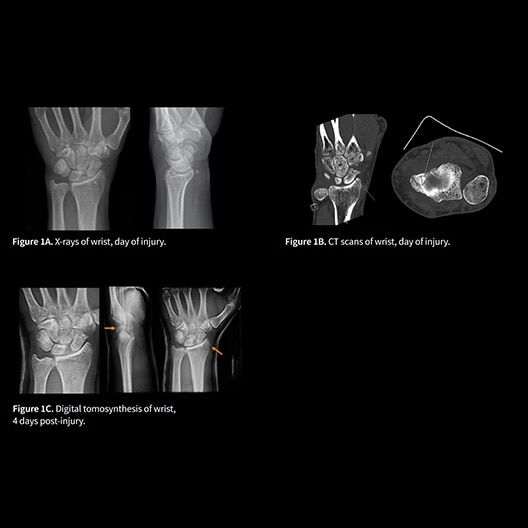

VolumeRAD™ digital tomosynthesis

Improves clinical diagnosis by removing overlaying structures and enhancing local tissue separation.

1. Geijer M et al. "Clinical utility of tomosynthesis in suspected scaphoid fracture: A pilot study" Skeletal Radiol. (Jul 2011): 40(7):863-7.